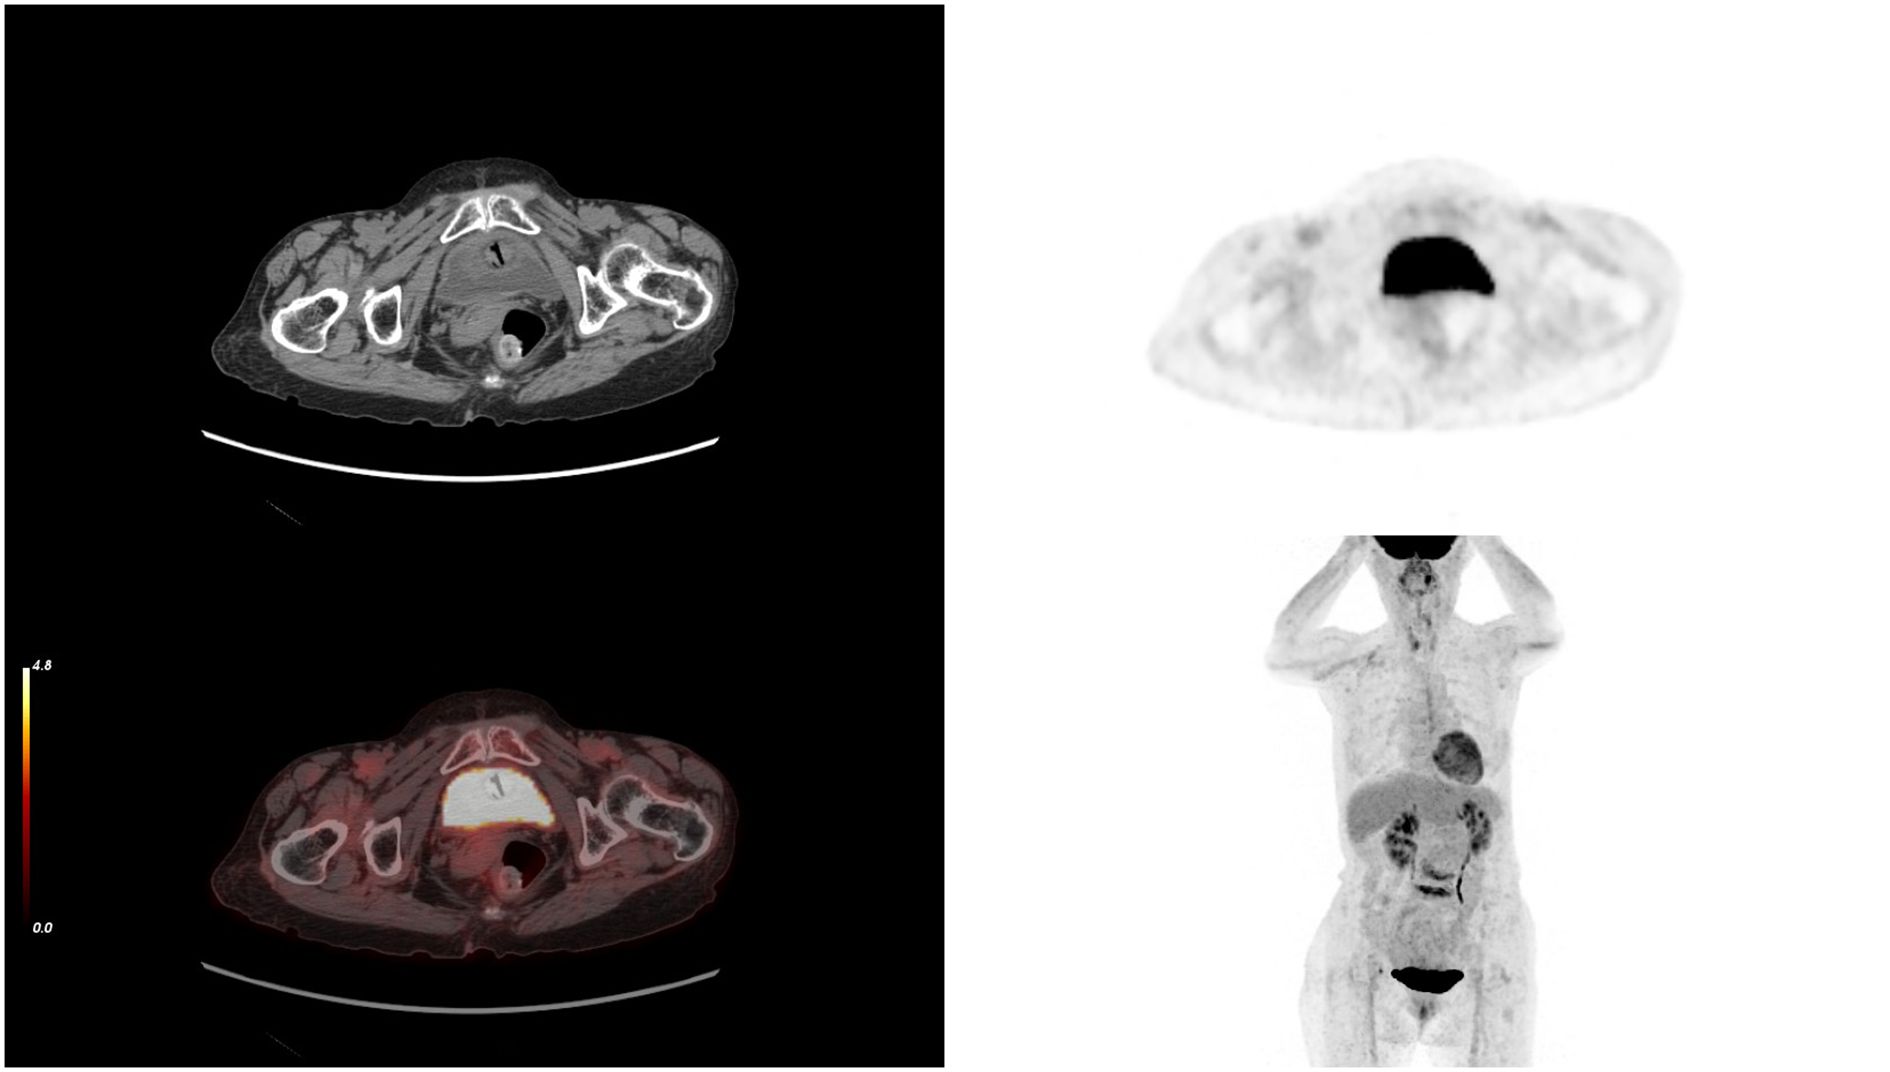

SCC is extremely rare and has a poor prognosis in advanced stage patients, with no evidence of survival benefit from radiotherapy and chemotherapy. We advised the patient to undergo genetic testing to identify potential therapeutic targets that could inform a more personalized treatment approach. The genetic testing of the patient’s tumor tissue revealed the following mutations and characteristics (1): Somatic tumor mutations:An NRAS Q61K mutation was detected at a frequency of 6%;A BRAF G464E mutation was identified at a frequency of 6.9%;An ABL1 K609del mutation was identified at a frequency of 6.0%; A DNMT3A S129G mutation was identified at a frequency of 48.2%; An EPCAM A82G mutation was identified at a frequency of 48.8%; A PALB2 A38G mutation was identified at a frequency of 42.5% (2). The tumor’s Combined Positive Score (CPS) for PD-L1 expression was 45, indicating positive programmed death-ligand 1 (PD-L1) expression (Figure 4) (3). No genes associated with hyperprogressive disease (HPD) were found (4). No mutations were detected in either immunotherapy-positive associated genes (MMR-related genes, POLE, POLD1, DDR genes, KRAS, TP53) or immunotherapy-negative associated genes (B2M, DNMT3A, JAK1/2, ALK, ROS1, MET, VEGFA, PTEN, STK11) (5). The microsatellite instability (MSI) testing results indicate a microsatellite stable (MSS) status, with an MSI score of 0.0235 (values ≥0.4 classified as MSI-H, <0.4 as MSS). The CPS for PD-L1 expression indicates that the tumor is highly likely to be sensitive to ICIs, which could make immunotherapy a viable treatment option. Prior to initiating formal antitumor therapy, the patient underwent comprehensive biochemical testing. The baseline characteristics upon hospital admission are detailed in Table 1. As a result, the patient was administered a combination therapy consisting of bevacizumab (300 mg) plus pembrolizumab (200 mg) Q3W. After 2 cycles of the therapeutic regimen, the tumor shrank significantly, and the patient did not experience any side effects(Figure 1B). Since then, the patient has continued to receive the regimen and the tumor has continued to shrink. Ultimately, after completing 10 cycles of treatment with ICIs and anti-angiogenic drugs, the positron emission tomography/computed tomography (PET-CT) scan showed complete disappearance of the tumor, with no evidence of residual cancer in the body(Figure 5). Considering the patient’s advanced stage and the high malignancy of cervical sarcomatoid carcinoma, which is highly prone to recurrence, we continued with the original treatment plan for maintenance therapy. During the maintenance therapy period, the patient underwent regular follow-up evaluations without evidence of recurrence. Treatment was maintained for 13 months until MRI demonstrated recurrence (Figure 6). Subsequently, the patient was transferred to the Department of Radiotherapy in our hospital and began radiotherapy. We still conducted regular follow-ups for the patient. Given the extremely high malignancy of this rare tumor, although the tumor eventually recurred unfortunately, the combination therapy initially achieved a transient recurrence-free survival period. Moreover, no significant adverse reactions were observed during the drug treatment. Radiotherapy was discontinued after 3 months due to concurrent tumor progression observed during treatment. The patient is currently receiving palliative care only. Our data demonstrate a progression-free survival (PFS) exceeding 13 months and overall survival (OS) surpassing 22 months.

Figure 5. After 10 cycles of treatment, PET-CT results showing the complete disappearance of the tumor. PET-CT, positron emission tomography/computed tomography.

The elderly female patient we admitted underwent 10 cycles of treatment with ICIs and anti-angiogenic drugs. Miraculously, the PET-CT scan data highlighted that the tumor had completely vanished, with no signs of cancer found throughout her body (Figures 5, 7). Considering the high malignancy of SCC, which is highly prone to recurrence, we continued with the original treatment plan for maintenance therapy.